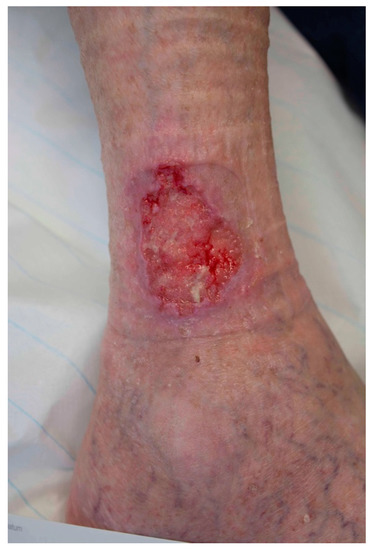

Malignant Tumours Presenting as Chronic Leg or Foot Ulcers